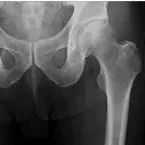

图文详解:股骨转子间骨折手术技巧!

本文未经授权禁止转载股骨转子间骨折多发生于老年人,国外文献报道,65岁以上老年人髋部骨折保守治疗,只有50%能恢复独立生活,恢复到伤前功能水平的仅25%,而手术治疗者80%以上的患肢功能恢复满意。因此国内外多数学者倾向于手术治疗,认为股骨转子间骨折患者只要身体条件许可就应积极治疗并发症,尽可能采用手术治疗。本文将介绍提升技术的一些手术技巧,与一例使用Gamma3 长钉内固定失败的病例分享,旨在与各位老师共同提升。...